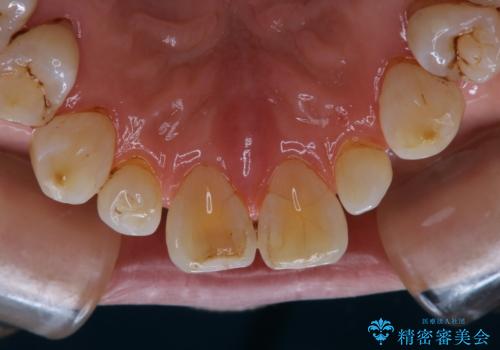

- クリーニングがかなり久しぶりで、全体的にきれいにして欲しいとのことで来院されました。全体的にステインの量がとても多かったため、施術前にご相談をし、60分コースでできる限りのステイン落としを行うこととなりました。今回は審美的に見える表側をメインでPMTCを行いました。

毎日丁寧に歯磨きをしていても、日常生活での飲食物などにより着色してしまうことはあります。PMTCでは、歯の表面の凸凹にミネラルを補給して、ツルツルの表面に仕上げます。定期的にPMTCを行うことにより、歯質の強化になり着色がつきにくい状態になります。